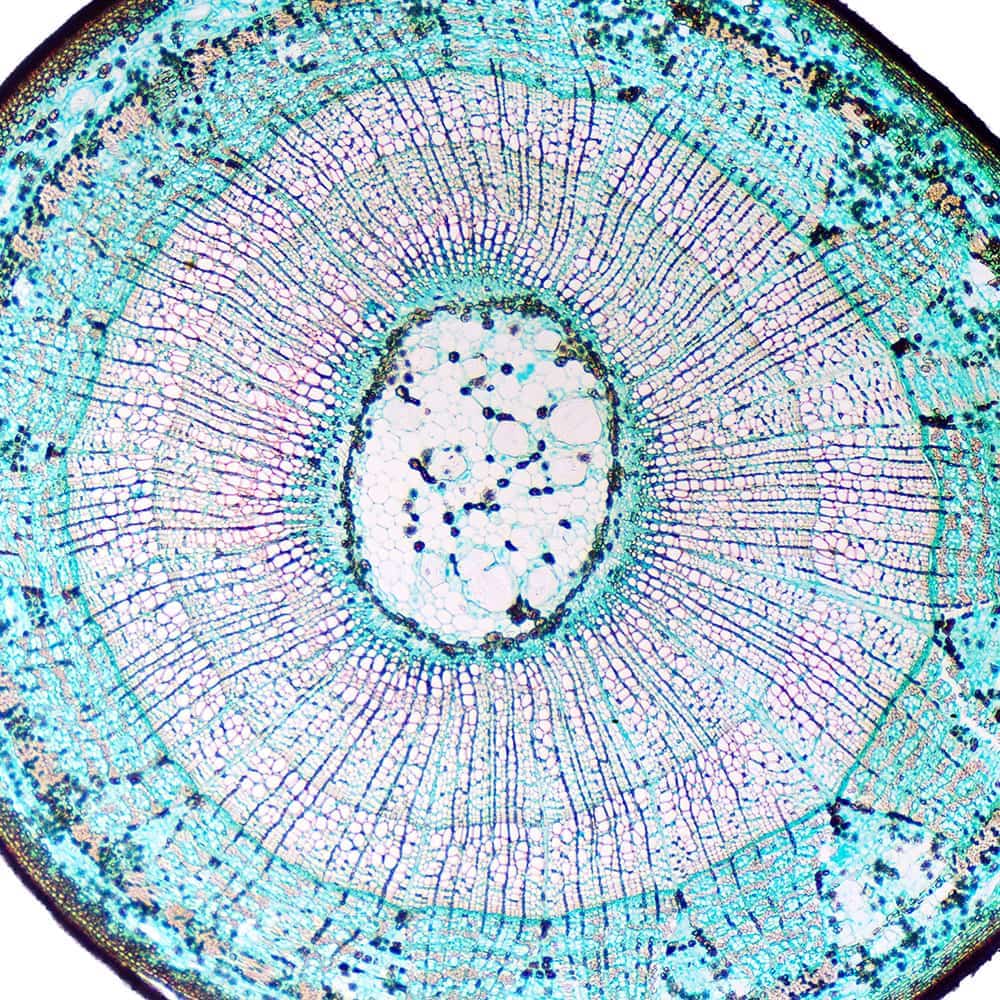

In der modernen präventiven Medizin hat die Darmgesundheit eine zentrale Bedeutung erlangt. Ein gesunder Darm ist nicht nur für die Verdauung wichtig, sondern beeinflusst maßgeblich unser Immunsystem, unsere Stimmung und unsere allgemeine Gesundheit. Eine besondere Herausforderung stellt dabei die Dünndarmfehlbesiedlung (SIBO) dar.

Der Darm als Zentrum der Gesundheit

- Immunsystem: Ein Großteil unseres Immunsystems ist im Darm angesiedelt. Eine vielfältige Darmflora, auch Mikrobiom genannt, ist entscheidend für die Abwehr von Krankheitserregern und die Vorbeugung von Autoimmunerkrankungen.

- Nährstoffaufnahme: Ein gesunder Darm sorgt für eine effiziente Aufnahme von Nährstoffen aus der Nahrung. Dies ist essenziell für Wachstum, Entwicklung und die Funktion aller Organe.

- Psychische Gesundheit: Die Darm-Hirn-Achse verbindet den Darm direkt mit dem Gehirn. Ein Ungleichgewicht im Darm kann sich auf die Stimmung auswirken und sogar zu Depressionen oder Angstzuständen beitragen.

- Entzündungsregulation: Chronische Entzündungen im Darm können das Risiko für zahlreiche Erkrankungen erhöhen, darunter Herz-Kreislauf-Erkrankungen, Diabetes und Krebs.